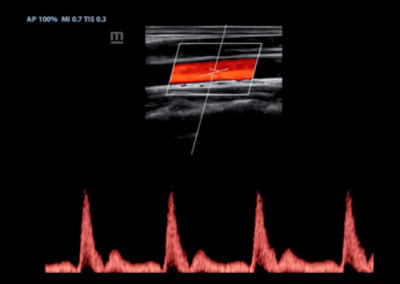

Z60

Sistema de diagnóstico ecográfico.

El sistema Z60 es una buena opción para aquellos que requieren un rendimiento de imagen de alta calidad, una movilidad simple y asequibilidad cuando se trata de imágenes ecográficas avanzadas. Con configuraciones completas y un diseño integrado, el Z60 es el resultado de los esfuerzos continuos y decididos de Mindray para hacer que la atención médica primaria sea más eficiente, eficaz y accesible para todos.